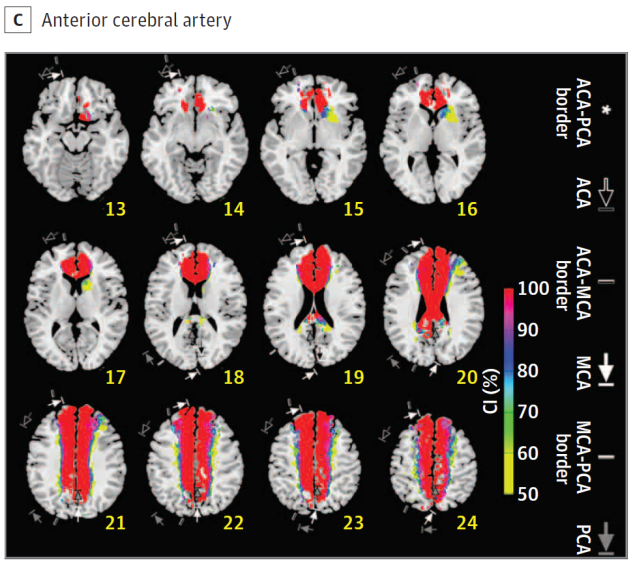

Cerebral vascular territories